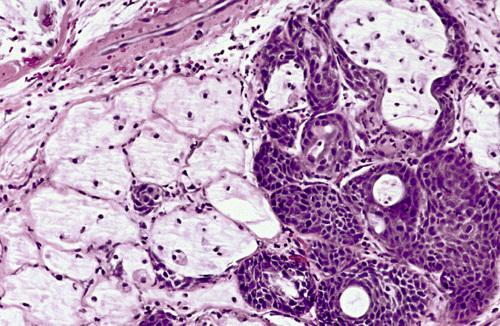

Necrotic mucous acini (left) and adjacent ductal squamous metaplasia (right). The overall lobular architecture of the involved glands is still preserved.

necrotizing sialometaplasia